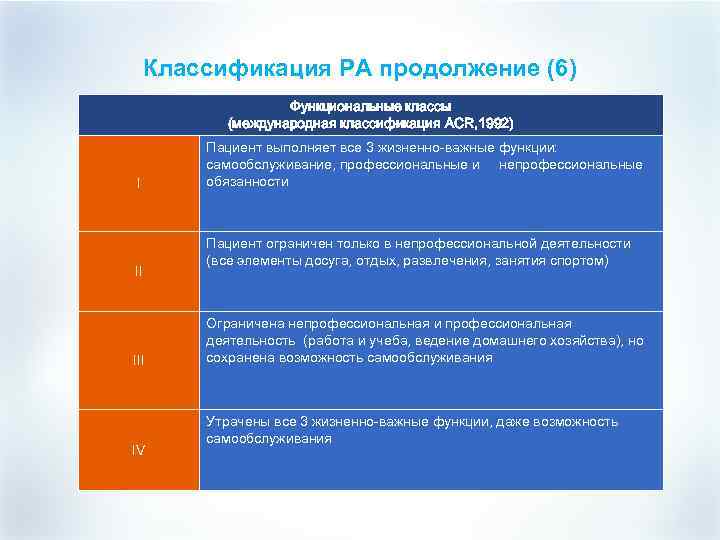

Классификация РА продолжение (6) Функциональные классы (международная классификация ACR, 1992) I II IV Пациент выполняет все 3 жизненно-важные функции: самообслуживание, профессиональные и непрофессиональные обязанности Пациент ограничен только в непрофессиональной деятельности (все элементы досуга, отдых, развлечения, занятия спортом) Ограничена непрофессиональная и профессиональная деятельность (работа и учеба, ведение домашнего хозяйства), но сохранена возможность самообслуживания Утрачены все 3 жизненно-важные функции, даже возможность самообслуживания

Классификация РА продолжение (6) Функциональные классы (международная классификация ACR, 1992) I II IV Пациент выполняет все 3 жизненно-важные функции: самообслуживание, профессиональные и непрофессиональные обязанности Пациент ограничен только в непрофессиональной деятельности (все элементы досуга, отдых, развлечения, занятия спортом) Ограничена непрофессиональная и профессиональная деятельность (работа и учеба, ведение домашнего хозяйства), но сохранена возможность самообслуживания Утрачены все 3 жизненно-важные функции, даже возможность самообслуживания